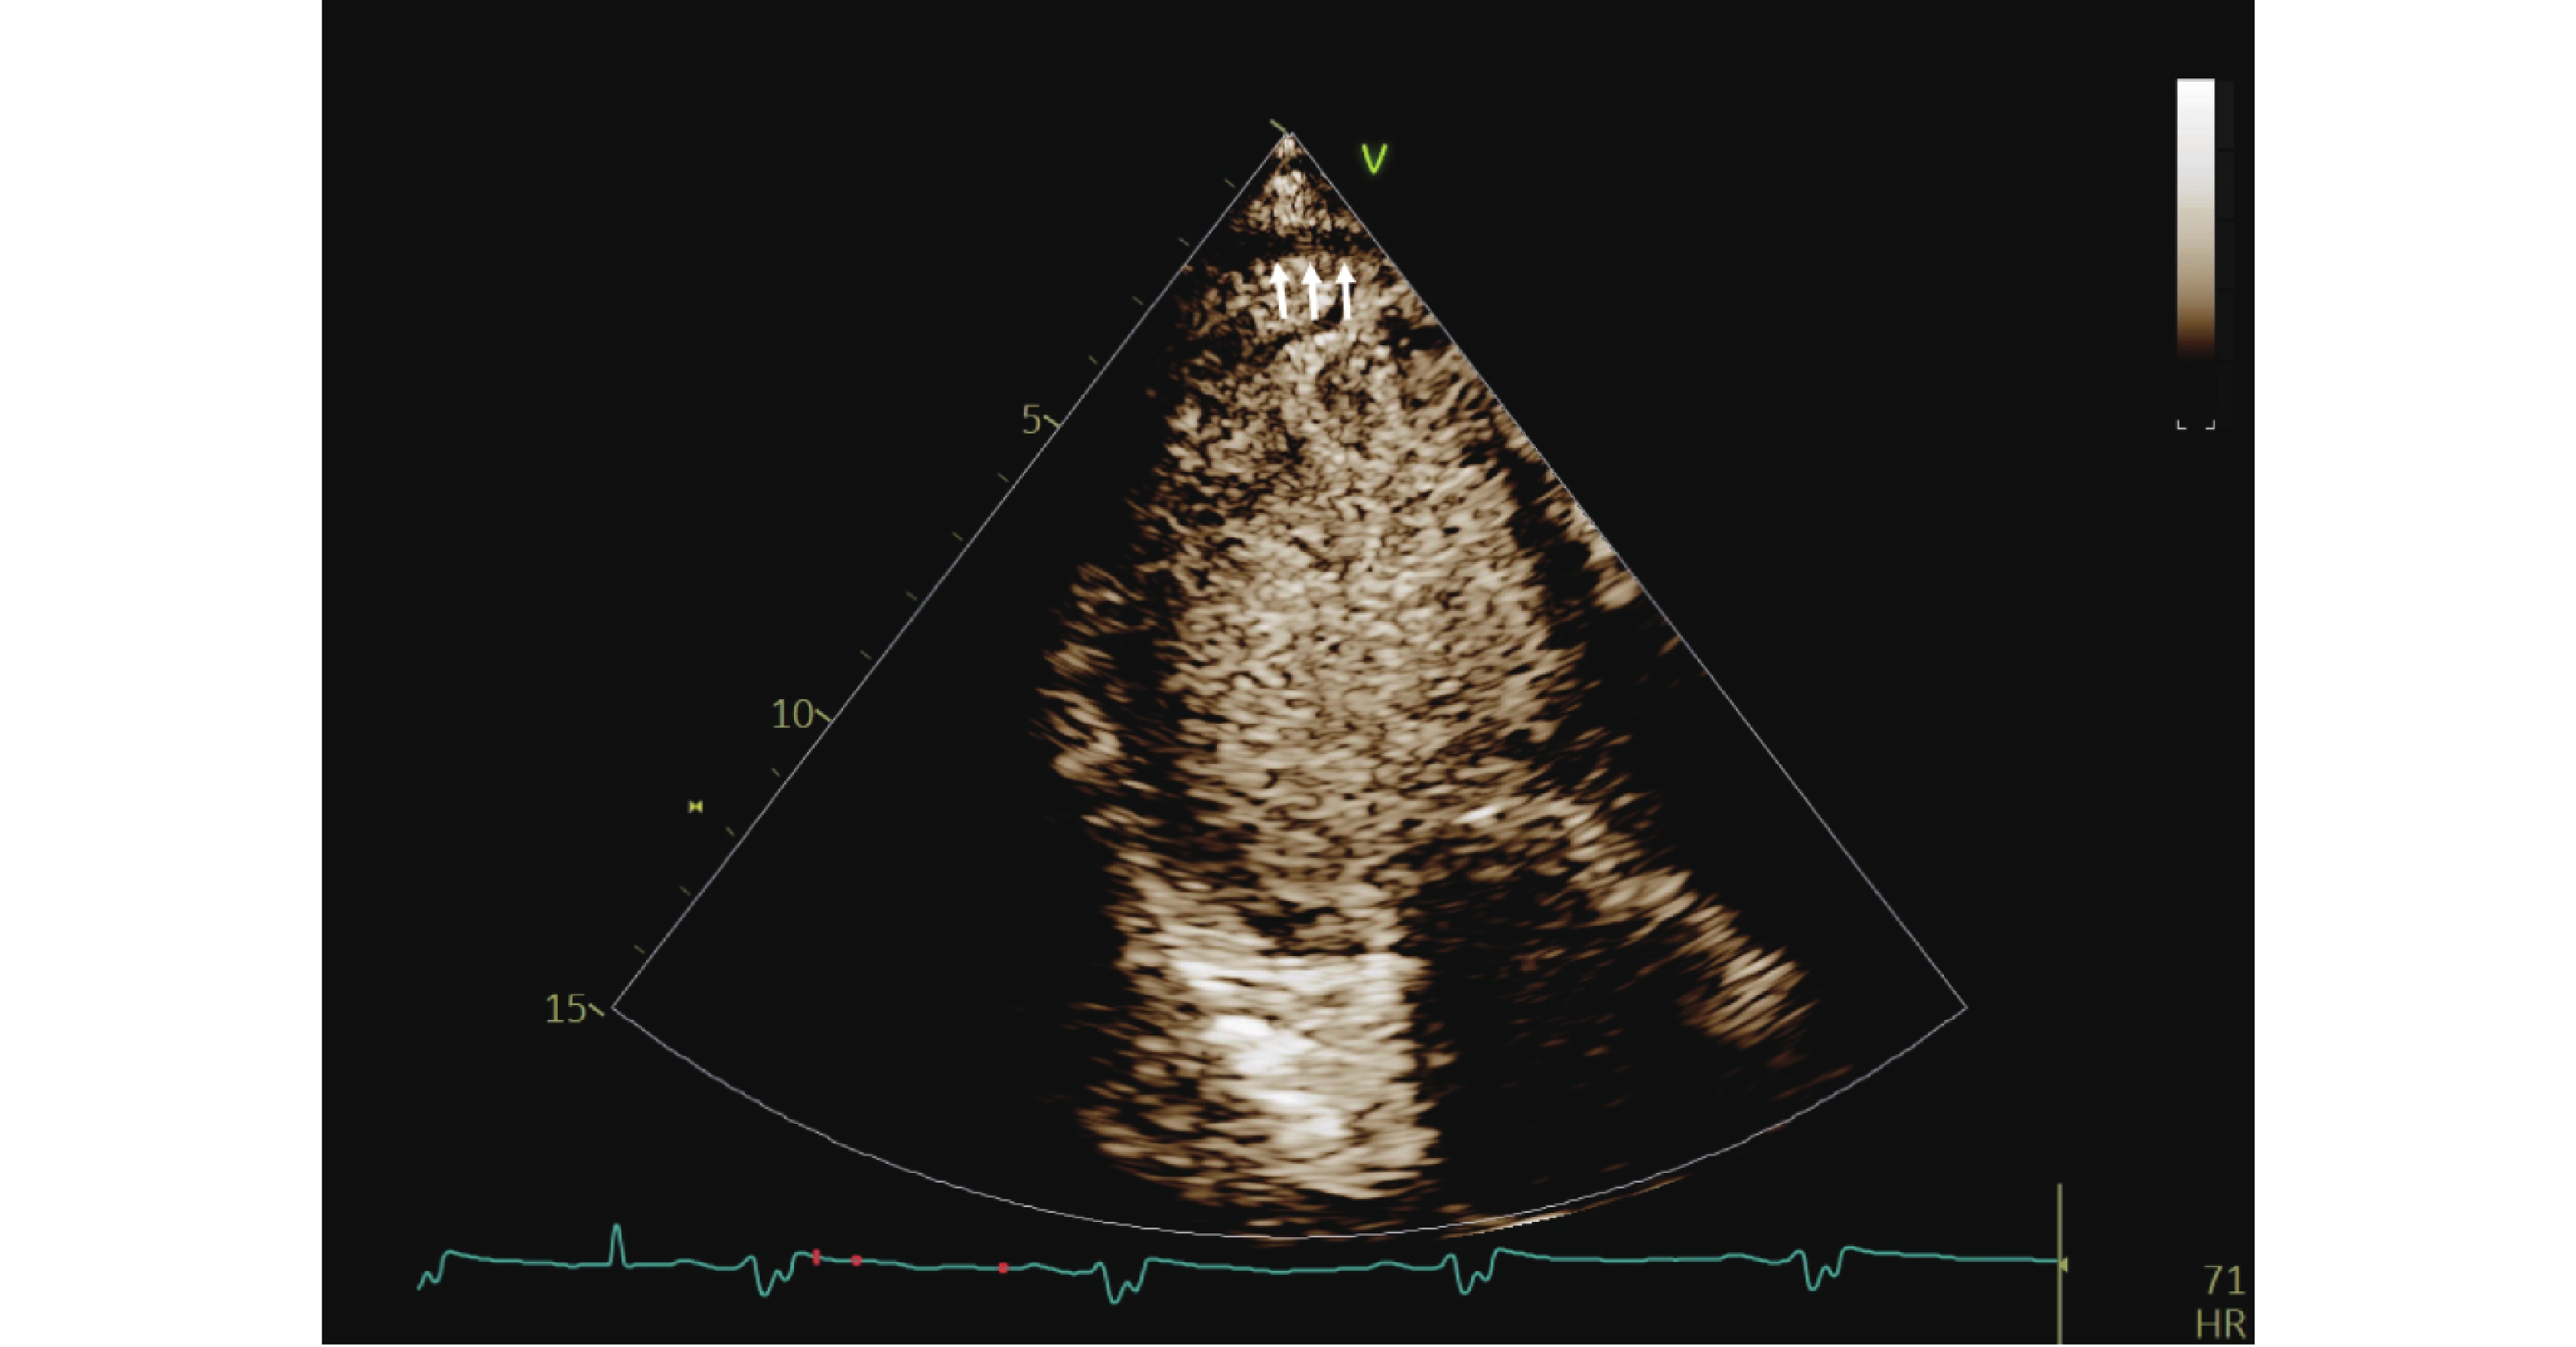

心肌超声造影心动图联合三维斑点追踪成像预测NSTEMI患者PCI术后主要心血管不良事件的风险

文婷, 曾令娇, 黄叶, 邱清勇, 朱玲玲

摘要(85) HTML(49) PDF (29)

摘要:

目的   探讨心肌超声造影心动图(myocardial contrast echocardiography,MCE)联合三维斑点追踪成像(three-dimensional speckle tracking imaging,3D-STI)对非ST段抬高型心肌梗死(non-ST-segment elevation myocardial infarction,NSTEMI)患者经皮冠状动脉介入治疗(percutaneous coronary intervention,PCI)术后主要心血管不良事件(major adverse cardiovascular events,MACEs)的预测作用。  方法   选取2022年5月至2024年3月中国人民解放军联勤保障部队第九二八医院254例NSTEMI患者,行PCI术,根据出院1年内MACEs发生情况分为MACEs组、无MACEs组,比较两组临床资料、常规超声心动图参数、MCE参数[平台期峰值强度(peak intensity,A)、灌注计分指数(perfusion score index,PSI)、曲线斜率(beta value,β)及心肌血流量(myocardial blood flow,A·β)]及3D-STI参数[左室整体面积应变(left ventricular global area strain,LVGAS)、左室整体环向应变(left ventricular global circumferential strain,LVGCS)、左室整体纵向应变(left ventricular global longitudinal strain,LVGLS)、左室整体径向应变(left ventricular global radial strain,LVGRS)]的差异;分析MCE、3D-STI参数与左室射血分数(left ventricular ejection fraction,LVEF)的关系;以受试者工作特征(receiver operating characteristic,ROC)曲线分析MCE、3D-STI参数预测MACEs的价值。  结果   与无MACEs组相比,MACEs组N末端脑钠肽前体(N-terminal pro-brain natriuretic peptide,NT-proBNP)、白介素-6(interleukin-6,IL-6)、可溶性生长刺激表达基因2蛋白(soluble suppression of tumorigenicity 2,sST2)较高,LVEF、血管内皮生长因子(vascular endothelial growth factor,VEGF)较低(P < 0.05);术后3个月与无MACEs组相比,MACEs组A、β、A·β较低,PSI较高,两组A、PSI、β、A·β术后3个月-术后24 h差值比较有统计学意义(P < 0.05);术后3个月MACEs组LVGAS、LVGCS、LVGLS、LVGRS均低于无MACEs组,两组LVGAS、LVGCS、LVGLS、LVGRS术后3个月-术后24 h差值比较有统计学意义(P < 0.05);术后3个月MCE、3D-STI参数联合预测MACEs的AUC为0.933(95%CI:0.895~0.961),术后3个月-术后24 h MCE、3D-STI参数差值联合预测MACEs的AUC为0.915(95%CI:0.873~0.946)。  结论   MCE、3D-STI定量参数联合对NSTEMI患者PCI术后MACEs风险有较高预测价值,监测术后3个月-术后24 h MCE及3D-STI参数的动态变化,有助于早期识别高风险患者,为制定个体化治疗与随访策略提供依据。